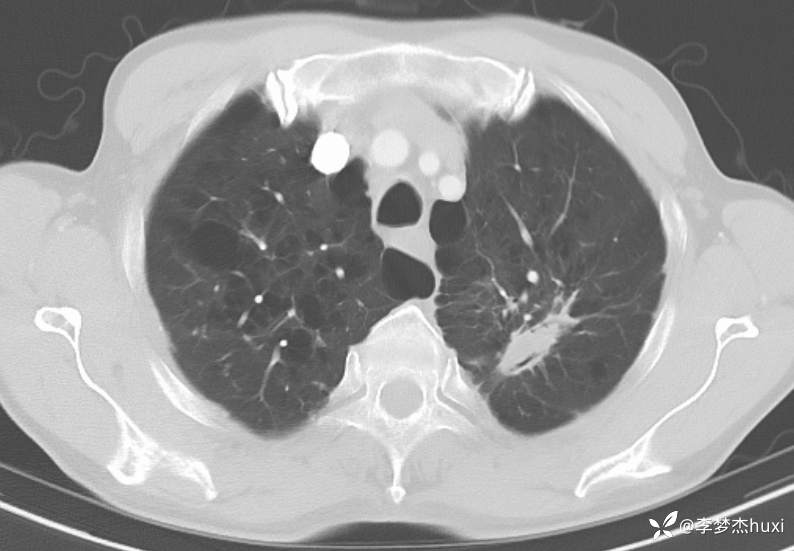

1.现病史:患者老年 男,患者于入院前7天“感冒”后出现咳嗽、咳痰,为白痰,不易咳出,伴胸闷憋气,活动后加重,病初发热,最高达38.0℃,无胸痛,无咯血,无腹痛、腹泻,无恶心、呕吐,无尿频、尿急、尿痛,院外给予口服药物(自诉口服药物,具体药物名称不详)治疗,病情无明显好转,6-13于我院门诊查胸部CT:左肺上叶软组织密度影-性质待定,双肺炎症,双肺气肿,双肺大泡,双肺部分实性结节-炎症?双肺实性结节,主动脉及冠状动脉钙化,双侧胸膜局限性增厚;肝脏多发囊性病变。6-14查胸部增强CT:左肺上叶空洞-真菌感染?占位不除外;双肺炎症,双肺气肿,双肺大泡,双肺部分实性结节-考虑炎症,双肺实性结节,主动脉及冠状动脉钙化,双侧胸膜局限性增厚;肝脏多发囊性病变;今日为进一步诊治来我院;门诊以“肺空洞”收入院。